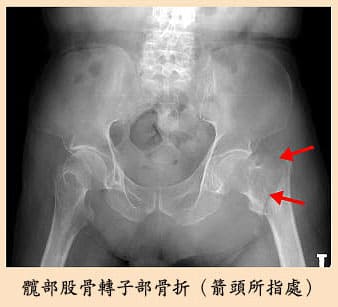

車禍肋骨與四肢骨折 無創傷手術